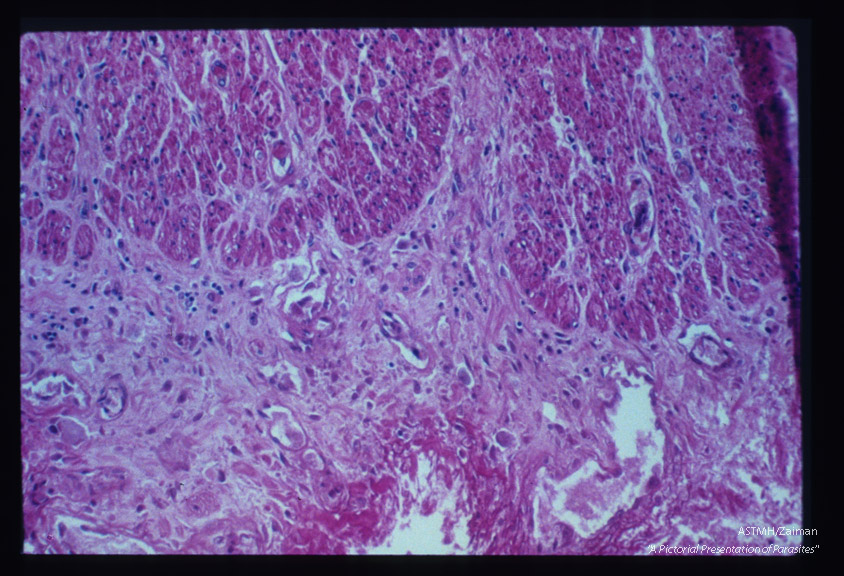

Chronic inflammatory response in region of bowel ulcer.

Entamoeba histolytica

Description: Chronic inflammatory response in region of bowel ulcer.